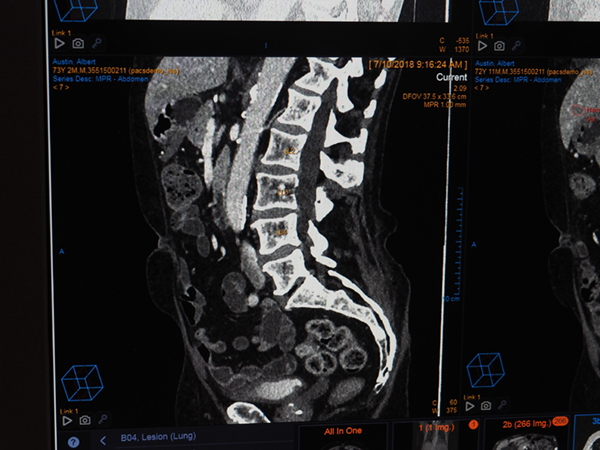

4) CTにおけるSpine labelingの自動化

椎体のラベリングをバックグラウンドで自動で実行し,画像上に表示する。

CTにおけるSpine labelingの自動化(W.I.P.)